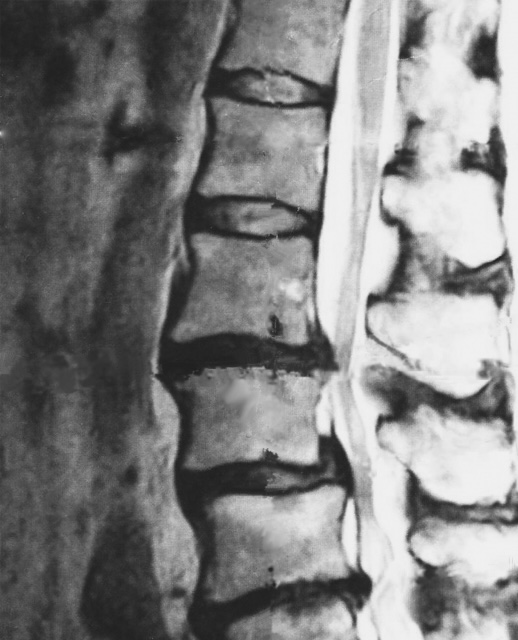

※画像はフリー素材であり、今回の患者のMRIではありません

脊椎の椎間板の問題は、加齢、外傷、あるいは日常的な活動によって引き起こされることがあります。脊柱の椎骨の間にあるゴムのようなクッションは、ストレスや損傷を受けると腫れたり、裂けたり、膨らんだりすることがあり、これが神経を圧迫する可能性があります。